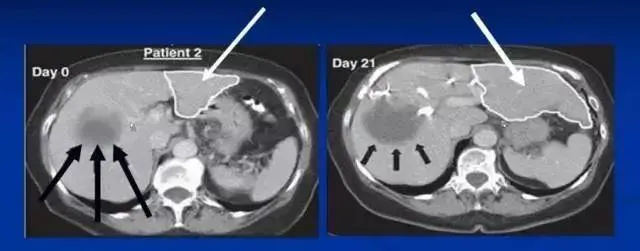

肝硬化是一種由慢性肝臟損傷引起的嚴(yán)重疾病,其特征是肝組織纖維化、肝小葉結(jié)構(gòu)破壞和肝功能衰退,可能導(dǎo)致肝功能失代償、肝癌及其他嚴(yán)重并發(fā)癥。干細(xì)胞治療肝硬化是一種新興的治療方法,近年來(lái)在臨床研究中顯示出顯著的潛力和效果。

沈陽(yáng)軍區(qū)總醫(yī)院消化內(nèi)科郭曉鐘等經(jīng)股動(dòng)脈肝內(nèi)自體骨髓干細(xì)胞移植治療肝硬化102例報(bào)告。

術(shù)后復(fù)查提示:

血漿蛋白改善在各項(xiàng)指標(biāo)中最顯著,其次為凝血功能的改善,可改善肝臟合成蛋白功能,對(duì)目前肝硬化腹水的患者具有積極意義。

第2個(gè)明顯改善的指標(biāo)為纖維蛋白原和凝血酶原時(shí)間,同樣代表肝臟的合成功能提高。